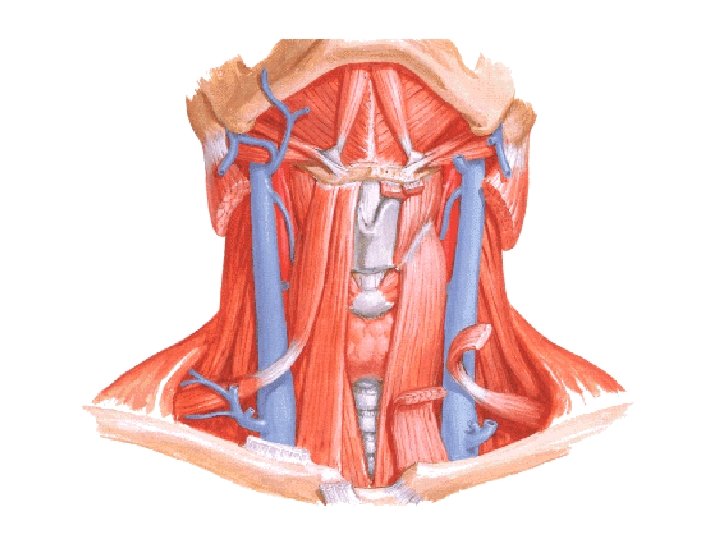

N. laryngeus sup. N. laryngeus inf. – N. laryngeus recurrens

A. laryngea sup. - A. thyroidea sup. A. laryngea inf. – A. thyroidea inf.